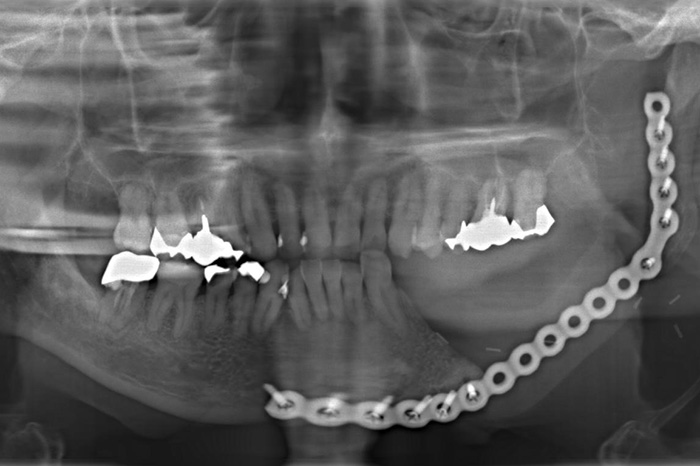

左側下顎水平埋伏智歯施術後

代表画像(下顎歯肉癌)

下顎歯肉癌

治療後(金属プレート再建+前腕皮弁再建)